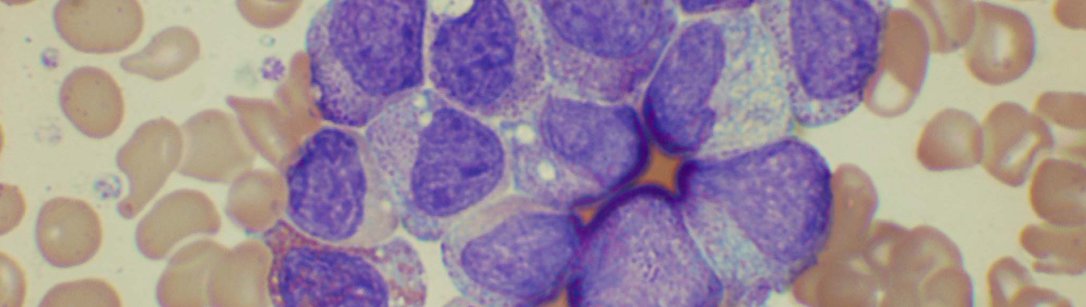

peripheral blood morphology

This course was created by Professor Barbara Bain at St Mary’s Hospital. It is now taught by Dr Vishal Jayakar.  Blood films showing a wide variety of abnormalities are available for microscopy and are subsequently discussed.